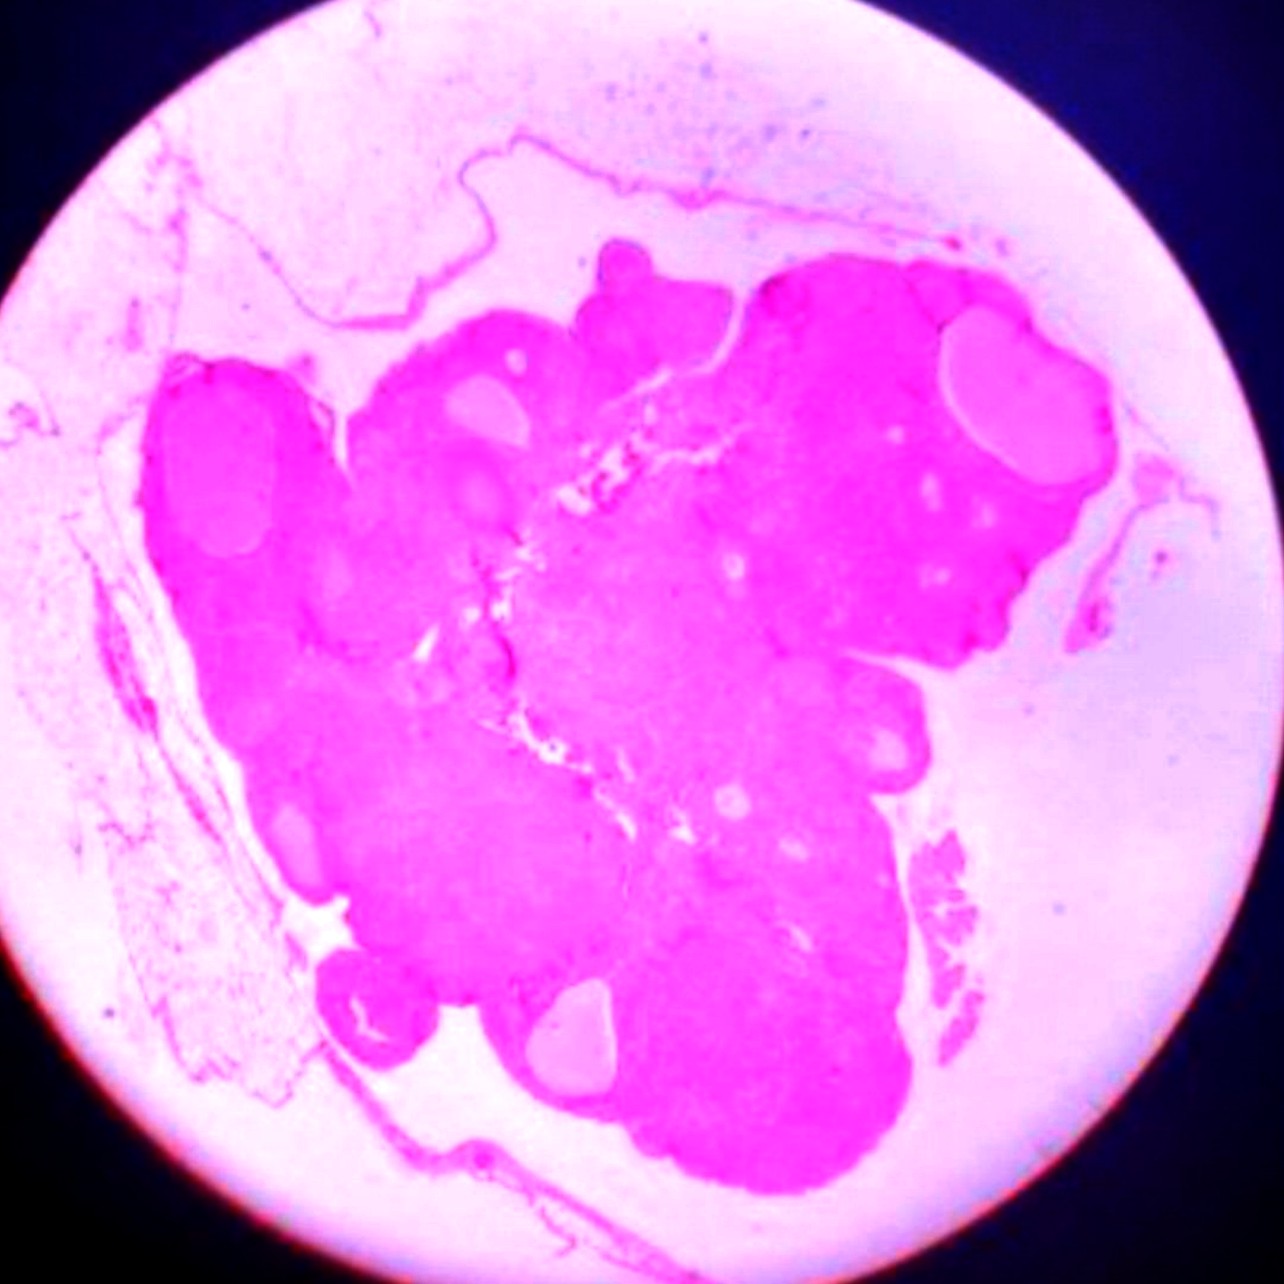

Ovary

Identification Points

1. Outer cortex-shows ovarian follicles in different

stages of development,primordial, primary,

secondary and Graafian follicle.

2. Inner medulla-contains connective tissue

with blood vessels.